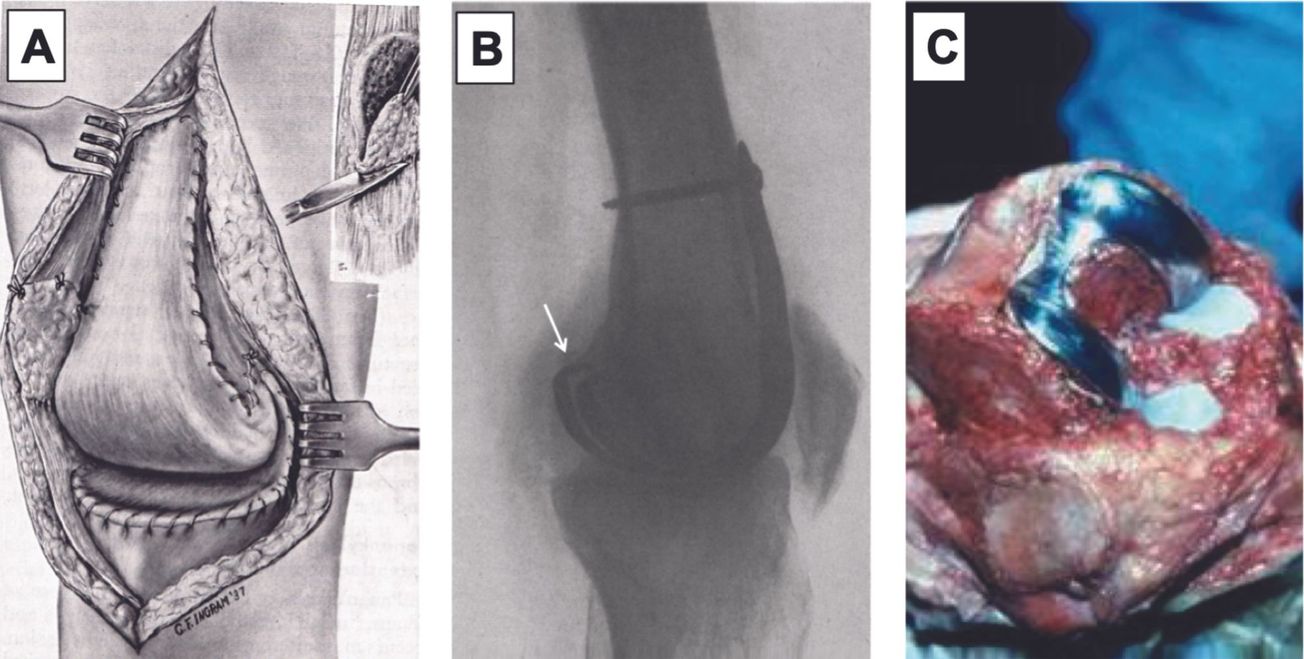

Mise au point Prise en charge actuelle des luxations épisodiques de la rotule (place de la reconstruction du ligament fémoro-patellaire médial) , Guillaume Demey Lyon Ortho Clinic - Clinique de la Sauvegarde, 29B avenue des Sources, 69009 Lyon, France , Elvire Servien Hôpital de la Croix-Rousse - HCL, Service de chirurgie orthopédique et de médecine du sport, FIFA medical center of excellence, Lyon, France , R. Debarge Centre Albert Trillat, Hôpitaux Lyon Croix Rousse, 8 rue de Margnolles, 69300 Lyon - Caluire , Sébastien Lustig Hôpital de la Croix-Rousse, Centre Albert Trillat, Lyon, France , Tarik Aït Si Selmi Centre Orthopédique SANTY, 24, avenue Paul Santy, 69008 Lyon, France , Philippe Neyret Hôpital de la Croix-Rousse, Centre Albert Trillat, Lyon, France N°186 - Septembre 2009 ● 19 min de lecture